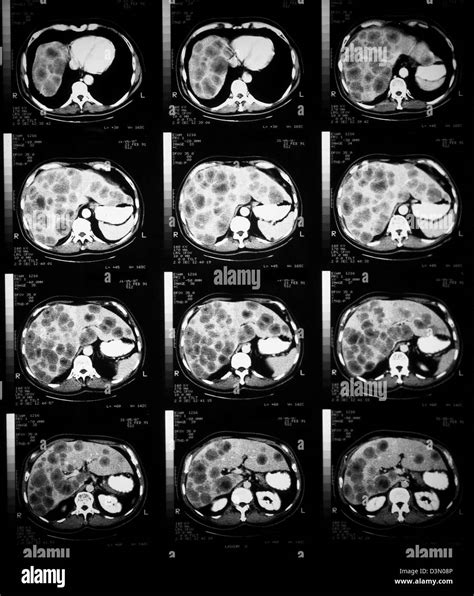

CT Scan Provides detailed cross-sectional images of the abdomen.

MRI Offers highly detailed imagery of soft tissues within the liver.